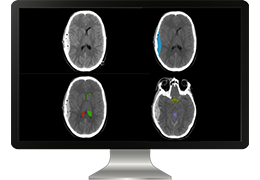

ART-Plan™ Artificial Intelligence Contouring